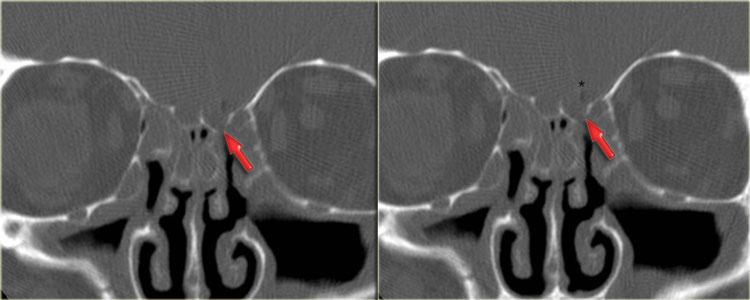

Bên trái là hình ảnh MRI tương ứng.

Các phát hiện bao gồm:

- Dịch trong xoang bướm phải (mũi tên đỏ).

- Mô giảm tín hiệu trong xoang bướm trái (mũi tên vàng).

- Lan rộng dọc theo bờ màng cứng của hố sọ giữa (mũi tên xanh dương).

- Lan rộng vào khoang gò má-cơ nhai trái (mũi tên vàng lớn).

- Sau tiêm thuốc tương phản từ, không có ngấm thuốc dạng đặc của mô trong khoang bướm.

Tiếp tục xem hình ảnh mặt phẳng coronal.

Hình ảnh mặt phẳng coronal của cùng bệnh nhân: T1 trước và sau tiêm thuốc tương phản từ.

Hình ảnh bình thường của hang Meckel bên phải; mô trong hang Meckel bên trái lan rộng vào xoang hang (mũi tên xanh dương).

Mũi tên đỏ chỉ vào bờ màng cứng của xoang hang: có ngấm thuốc ở cả hai mặt của màng cứng.

Bệnh lý bao quanh thùy thái dương (mũi tên xanh lá) và lan xuống dưới qua lỗ bầu dục (mũi tên vàng) vào khoang cơ nhai.

Dấu hoa thị chỉ mô bình thường không ngấm thuốc trong khoang cơ nhai.

Bệnh nhân này bị u lympho.

Chín trong mười trường hợp, bệnh nhân suy giảm miễn dịch sẽ bị nhiễm nấm, một trong mười trường hợp sẽ là u lympho.

CT và MRI có vai trò bổ sung cho nhau trong trường hợp này, nhưng cuối cùng cần sinh thiết để phân biệt hai chẩn đoán này, vì phương pháp điều trị khác nhau.